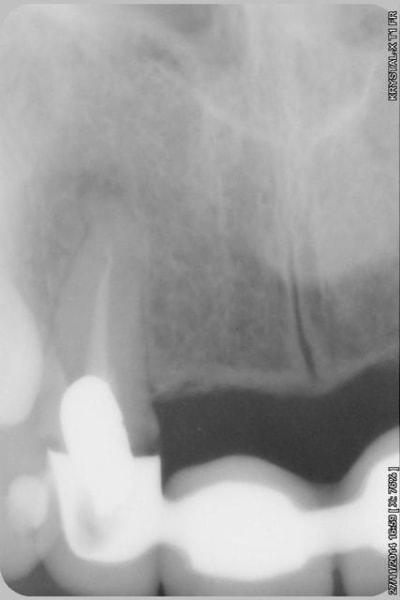

la suite

reconstitution, taille pour empreinte et provisoire (pas beau mais il sera remplacé)